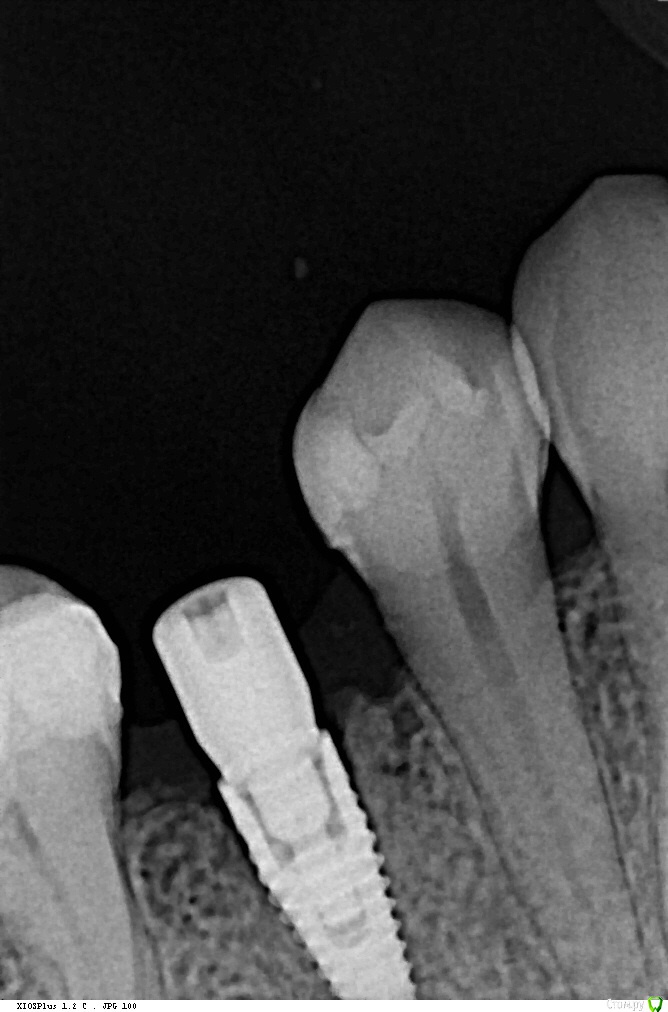

Кариес+ Опубликовано 26 июля, 2016 Поделиться Опубликовано 26 июля, 2016 Добрый день уважаемые коллеги. В область отсутствующего зуба 45 одномоментно после удаления был установлен имплантат нобель 3.5 с торком 35. Первый снимок сразу после установки, вторые через два месяца спустя Ссылка на комментарий

Кариес+ Опубликовано 26 июля, 2016 Автор Поделиться Опубликовано 26 июля, 2016 Смущает щель между импл и костью . Фиброинтеграция или незрелая не рентгеноконтрасная кость? Ссылка на комментарий

Доктор Хаус Опубликовано 4 августа, 2016 Поделиться Опубликовано 4 августа, 2016 Ой тест делать с анестезией ? Вот если случай без фдм а с заглушкой ? Небольшую инфильтрацию дать чтобы заглушку убрать и поставить имплантовод и дать нагрузку в 30-35н/см ?Даже с проводниковой анестезией будет больно, если произошла фиброинтеграция . А она происходит от того костное ложе перегрето или косное ложе не конгруэнтно самому имплантату . Для себя я четко усвоил что при одномоментный имплантации около 4 х мм имплантата должно быть в кости . По прицельным снимкам у меня сложилось впечатление что имплантат закручен в лунку. И костного ложа , здесь как такового нету . Вполне вероятно, что здесь произошла фибро интеграция ( неприжился) и поэтому на прицельном снимке вокруг имплантата определяется зона пониженной плотности. Ссылка на комментарий

Доктор Добрых Дел Опубликовано 6 августа, 2016 Поделиться Опубликовано 6 августа, 2016 Вообще не вижу разницы между 3мя снимками. И на первом и на втором видна "щель". Ссылка на комментарий